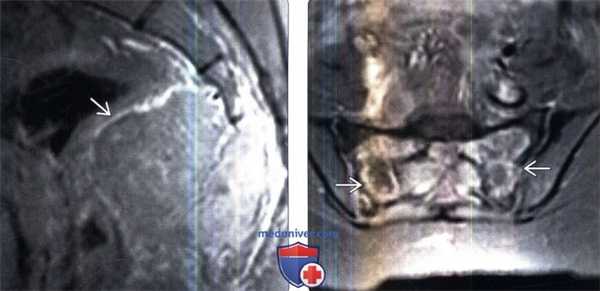

(Слева) МРТ, сагиттальная проекция, режим T1: полный коллапс тела позвонка L3 с сохранением межпозвонкового дискового пространства. Патологический очаг несколько гиперинтенсивен по отношению к скелетной мышце, характеризуется эпидуральным расширением и крупным передним параспинальным мягкотканным компонентом. Была подтверждена высоко агрессивная, но доброкачественная ГКО.

(Справа) МРТ, сагиттальная проекция, режим Т2: у этого же пациента визуализируется эпидуральное образование и параспинальный компонент с преимущественно низкоинтенсивным сигналом. ГКО преимущественно развивается в теле позвонка, а не в задних элементах и имеет подобные характеристики сигнала. (Слева) МРТ, аксиальная проекция, режим Т1 с подавлением сигнала от жира, с контрастным усилением у того же пациента: определяется диффузное контрастное усиление параспинального компонента. Обратите также внимание на поражение полой вены крупным интравенозным компонентом с аналогичными характеристиками сигнала. Была подтверждена высоко агрессивная, но доброкачественная ГКО.

(Справа) Рентгенография в ПЗ проекции: умеренно агрессивная опухоль, представленная полностью литическим очагом, который хорошо отграничен на большем протяжении, но дистально имеет проникающий характер с широкой переходной зоной. Расположение и лучевые признаки типичны для агрессивной ГКО. (Слева) КТ, аксиальная проекция, без контрастного усиления: у этого же пациента подтверждается агрессивность очага. Визуализируются признаки прорыва переднего кортикального слоя с небольшим мягкотканным компонентом. Очаг может соответствовать ГКО, однако следует рассматривать вероятность более агрессивных новообразований.

(Справа) МРТ, аксиальная проекция, режим Т2: у этого же пациента визуализируются высокоинтенсивные зоны, по большей степени разделенные перемычками. Обратите внимание на уровни жидкости. Признаки не типичны для ГКО, поэтому следует рассматривать вероятность телеангиэктатической остеосаркомы. Во время хирургического вмешательства была подтверждена кистозная форма ГКО с участками аневризмальной костной кисты.